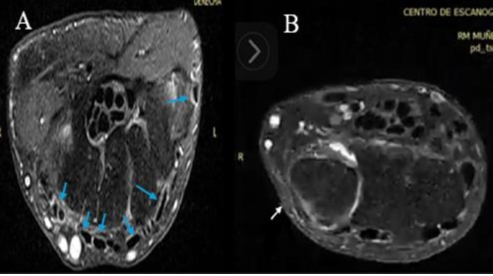

Hombre de 63 años, sin antecedentes de importancia, con cuadro de tres meses de dolor en región dorsal del antebrazo y con dificultad para movimientos biomecánicos de la articulación de la muñeca radiocarpiana, niega algún tipo de trauma previo. En el examen físico presentaba signos vitales normales. Se evidenció edema en antebrazo, dolor en punto de inserción del tendón carpi ulnaris y en la base del quinto metacarpiano. Se ordenaron imágenes; la ecografía demostró engrosamiento del ECU, la resonancia magnética describió hallazgos de discontinuidad distal cerca al punto de inserción en la base del quinto metacarpiano (Figura 1). Ante los hallazgos, consideran al paciente candidato para reinserción con injerto tendinoso.

Figura 1: RM A: Compartimientos anatómicos de los tendones en la articulación radiocarpiana (Flechas azules). B: Evidencia la ruptura tendón carpi ulnaris (Flecha blanca)